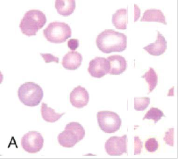

Patofyziologie: fragmentace krvinek – schistocyty – zvýšený zánik ve slezině, při intravaskulární hemolýze + současně aktivace koagulačního systému – DIC s tvorbou mikrotrombů v cirkulaci

• ↑schistocyty, akantocyty, sférocyty

• ↑ počet schistocytů

• pancytopenie s leukoerytroblastickou reakcí a přítomnosti slzičkovitých ERY